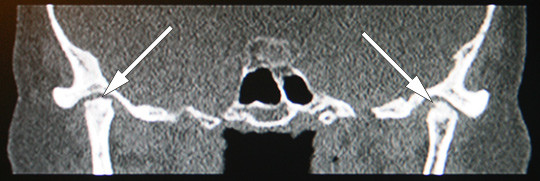

I figur 3 og 4 ser vi et CT-bilde av kjeveleddene og ortopantomogram (OPG) av mandibula hos vår pasient, som viser nærmest fullstendig destruksjon av kondylene på begge sider, noe som forklarer den betydelige retrusjonen av mandibula og bittåpning i fronten på hele fem millimeter. Både det kliniske og det røntgenologiske bildet er forskjellig fra det man vanligvis finner ved kjeveleddsartrose, en lidelse som stort sett er begrenset til leddbrusken og det periartikulære beinet. I dette tilfellet er hele kondylen destruert.